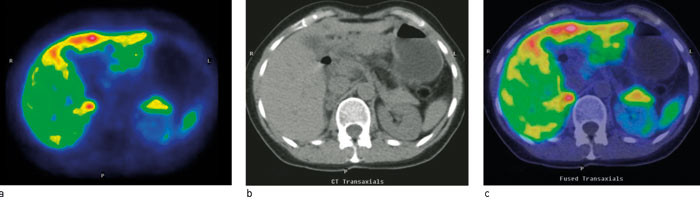

11C-hydroksytryptofan (11C-5-HPT) er et radiofarmakon utviklet ved Universitetet i Uppsala. 11C-5-HTP akkumuleres spesifikt i svulster som produserer eller kan produsere serotonin (13) – (17). 11C-5-HTP-PET viser derfor høyt opptak i en rekke forskjellige nevroendokrine svulster som f.eks. de karsinoide (fig 1), øycellepancreastumorer, men også ikke-funksjonelle endokrine pancreastumorer (13). 11C-5-HPT-PET er bedre enn CT, somatostatinreseptorscintigrafi og er også rapportert bedre enn 18F-DOPA-PET for nevroendokrine svulster i pancreas. Spesielt kan relativt små lesjoner påvises (14, 15). Undersøkelsen er mest relevant for å kartlegge usikre lesjoner ved planlagt kurativ metastasekirurgi og ved utredning av suspekt klinisk residiv som ikke lar seg påvise med CT og scintigrafi. Ytterligere indikasjon for 11C-5-HPT-PET er oppfølging av behandling når resultatene av radiologiske, biokjemiske og kliniske undersøkelser divergerer.